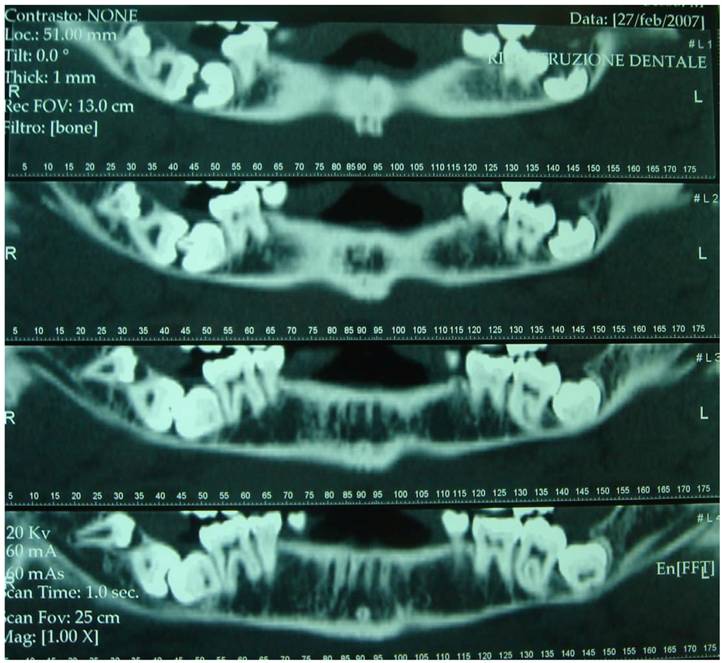

Figure 4

X-Ray Dental Panoramic Tomogram (elder sister)

In agreement with the international literature, the Authors opted to leave the sisters' supernumerary teeth in situ, as there were not any signs or symptoms justifying the extraction therapy. Whereas the patient who first came to our attention was subjected to extraction of teeth 4.7, 4.8 and 4.9, after a routine hematological investigation and after the assessment of radiographic exams, such as X-Ray Dental Panoramic Tomogram and Denta-Scan (Fig. 6) of the inferior maxillary bone. Exodontia led to remission of the algic symptomathology, without compromising somesthesia in the treated region, although the extracted teeth were in the close proximity of the inferior mandibular canal.

Figure 6

Dental-Scan of the mandibular bone (proband)